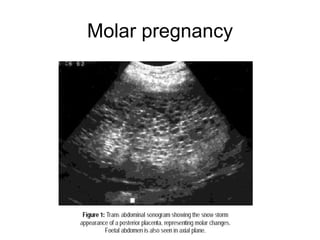

MOLAR PREGNANCY Same concept with miscarriage Uterus bigger than dates USS features suggestive Require S&C – expect massive blood loss, 2 large bore IV lines, GXM 2 units and under GA For uterus > 12 weeks (perform in Specialist hospital) HPE & regular serum beta hCG Follow up for 2 years Not to conceive for at least 1year

Molar pregnancy

MOLAR PREGNANCY Sameconcept with miscarriage Uterus bigger than dates USS features suggestive Require S&C – expect massive blood loss, 2 large bore IV lines, GXM 2 units and under GA For uterus > 12 weeks (perform in Specialist hospital) HPE & regular serum beta hCG Follow up for 2 years Not to conceive for at least 1year